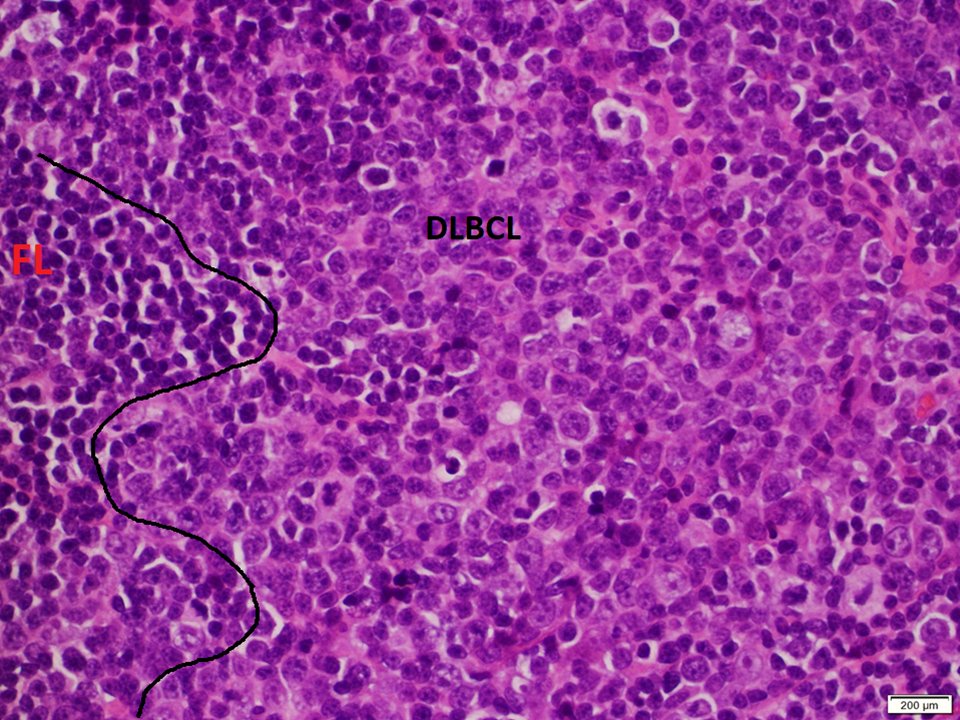

(1/3) Mutlifocal DLBCL arising in a background of low grade follicular lymphoma, with a peculiar architecture #hemepath #LJMFridayUnknowns #VirtualHemepathMDA #lymsm #endcancer

(3/3) High power view of the large cell transformation component (with numerous centroblasts and immunoblasts), and adjacent FL component #hemepath #LJMFridayUnknowns #VirtualHemepathMDA #lymsm #endcancer